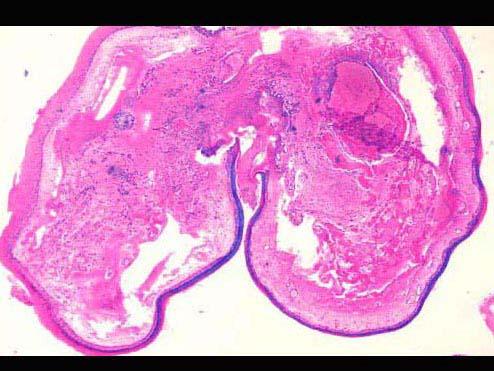

问题 患者,男,40岁,声嘶1周,喉镜见左侧声带前1/3和后2/3交界处有一黄白色圆形肿物,约1.3cm×1cm×0.7cm大小,活检镜下如图,该患者的正确诊断是 ( )

选项 A.声带息肉 B.声带小结 C.喉纤维瘤 D.喉血管瘤 E.声带癌

答案 A